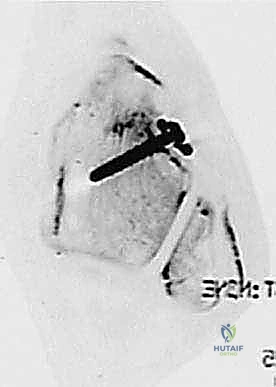

الخطوة الرابعة: تمرير الطعم وتثبيته (Graft Passage and Fixation)

يتم تمرير الطعم الذاتي (وتر الرشيق المُجهز) عبر الأنفاق العظمية بمسار يحاكي تماماً المسار الطبيعي للأربطة (ATFL و CFL). هذه التقنية التشريحية تضمن استعادة الحركة الطبيعية للكاحل دون تقييد.

يتم بعد ذلك تثبيت الطعم بقوة داخل العظام باستخدام براغي تداخلية (Interference Screws). هذه البراغي مصنوعة من مواد حيوية متقدمة (Bio-absorbable أو PEEK) تندمج مع العظم بمرور الوقت. يتم شد الطعم بالدرجة المناسبة (Tensioning) بينما تكون القدم في وضعية محايدة لضمان أقصى درجات الثبات.